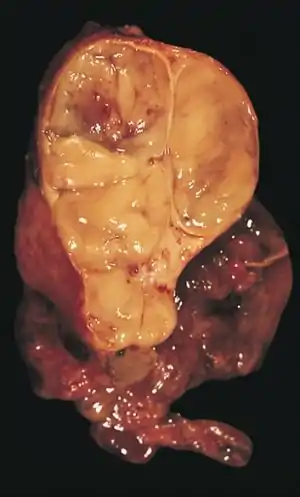

| An encapsulated thymoma (mixed lymphocytic and epithelial type) | |

An encapsulated cystic thymoma.

A locally invasive circumscribed thymoma (mixed lymphocytic and epithelial, mixed polygonal and spindle).